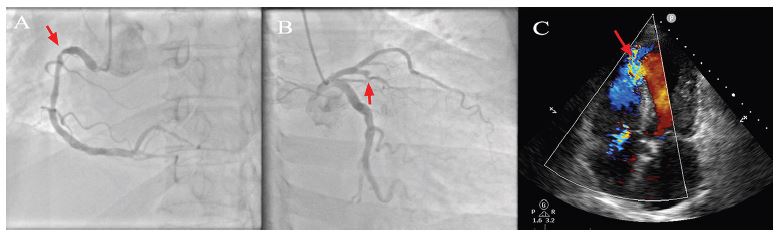

The electrocardiogram (ECG) showed an extensive anterior wall ST segment elevation compatible with MI. After failed thrombolysis with tenecteplase (no changes in ECG), the patient was transferred to another institution for a more complex care. Twenty-four hours after emergency room (ER) consultation, coronary angiography showed severe two-vessel disease with complete obstruction of proximal anterior descending artery (ADA) and 80% obstruction of proximal right coronary artery (RCA). Percutaneous angioplasty of ADA was unsuccessful. An apical VSD was discovered during the procedure. Echocardiography confirmed the VSD, with left ventricular ejection fraction (LVEF) of 40% (Figure 1, Videos 1 and 2). Therefore, the patient was transferred to our center for coronary artery bypass grafting surgery and VSD repair.